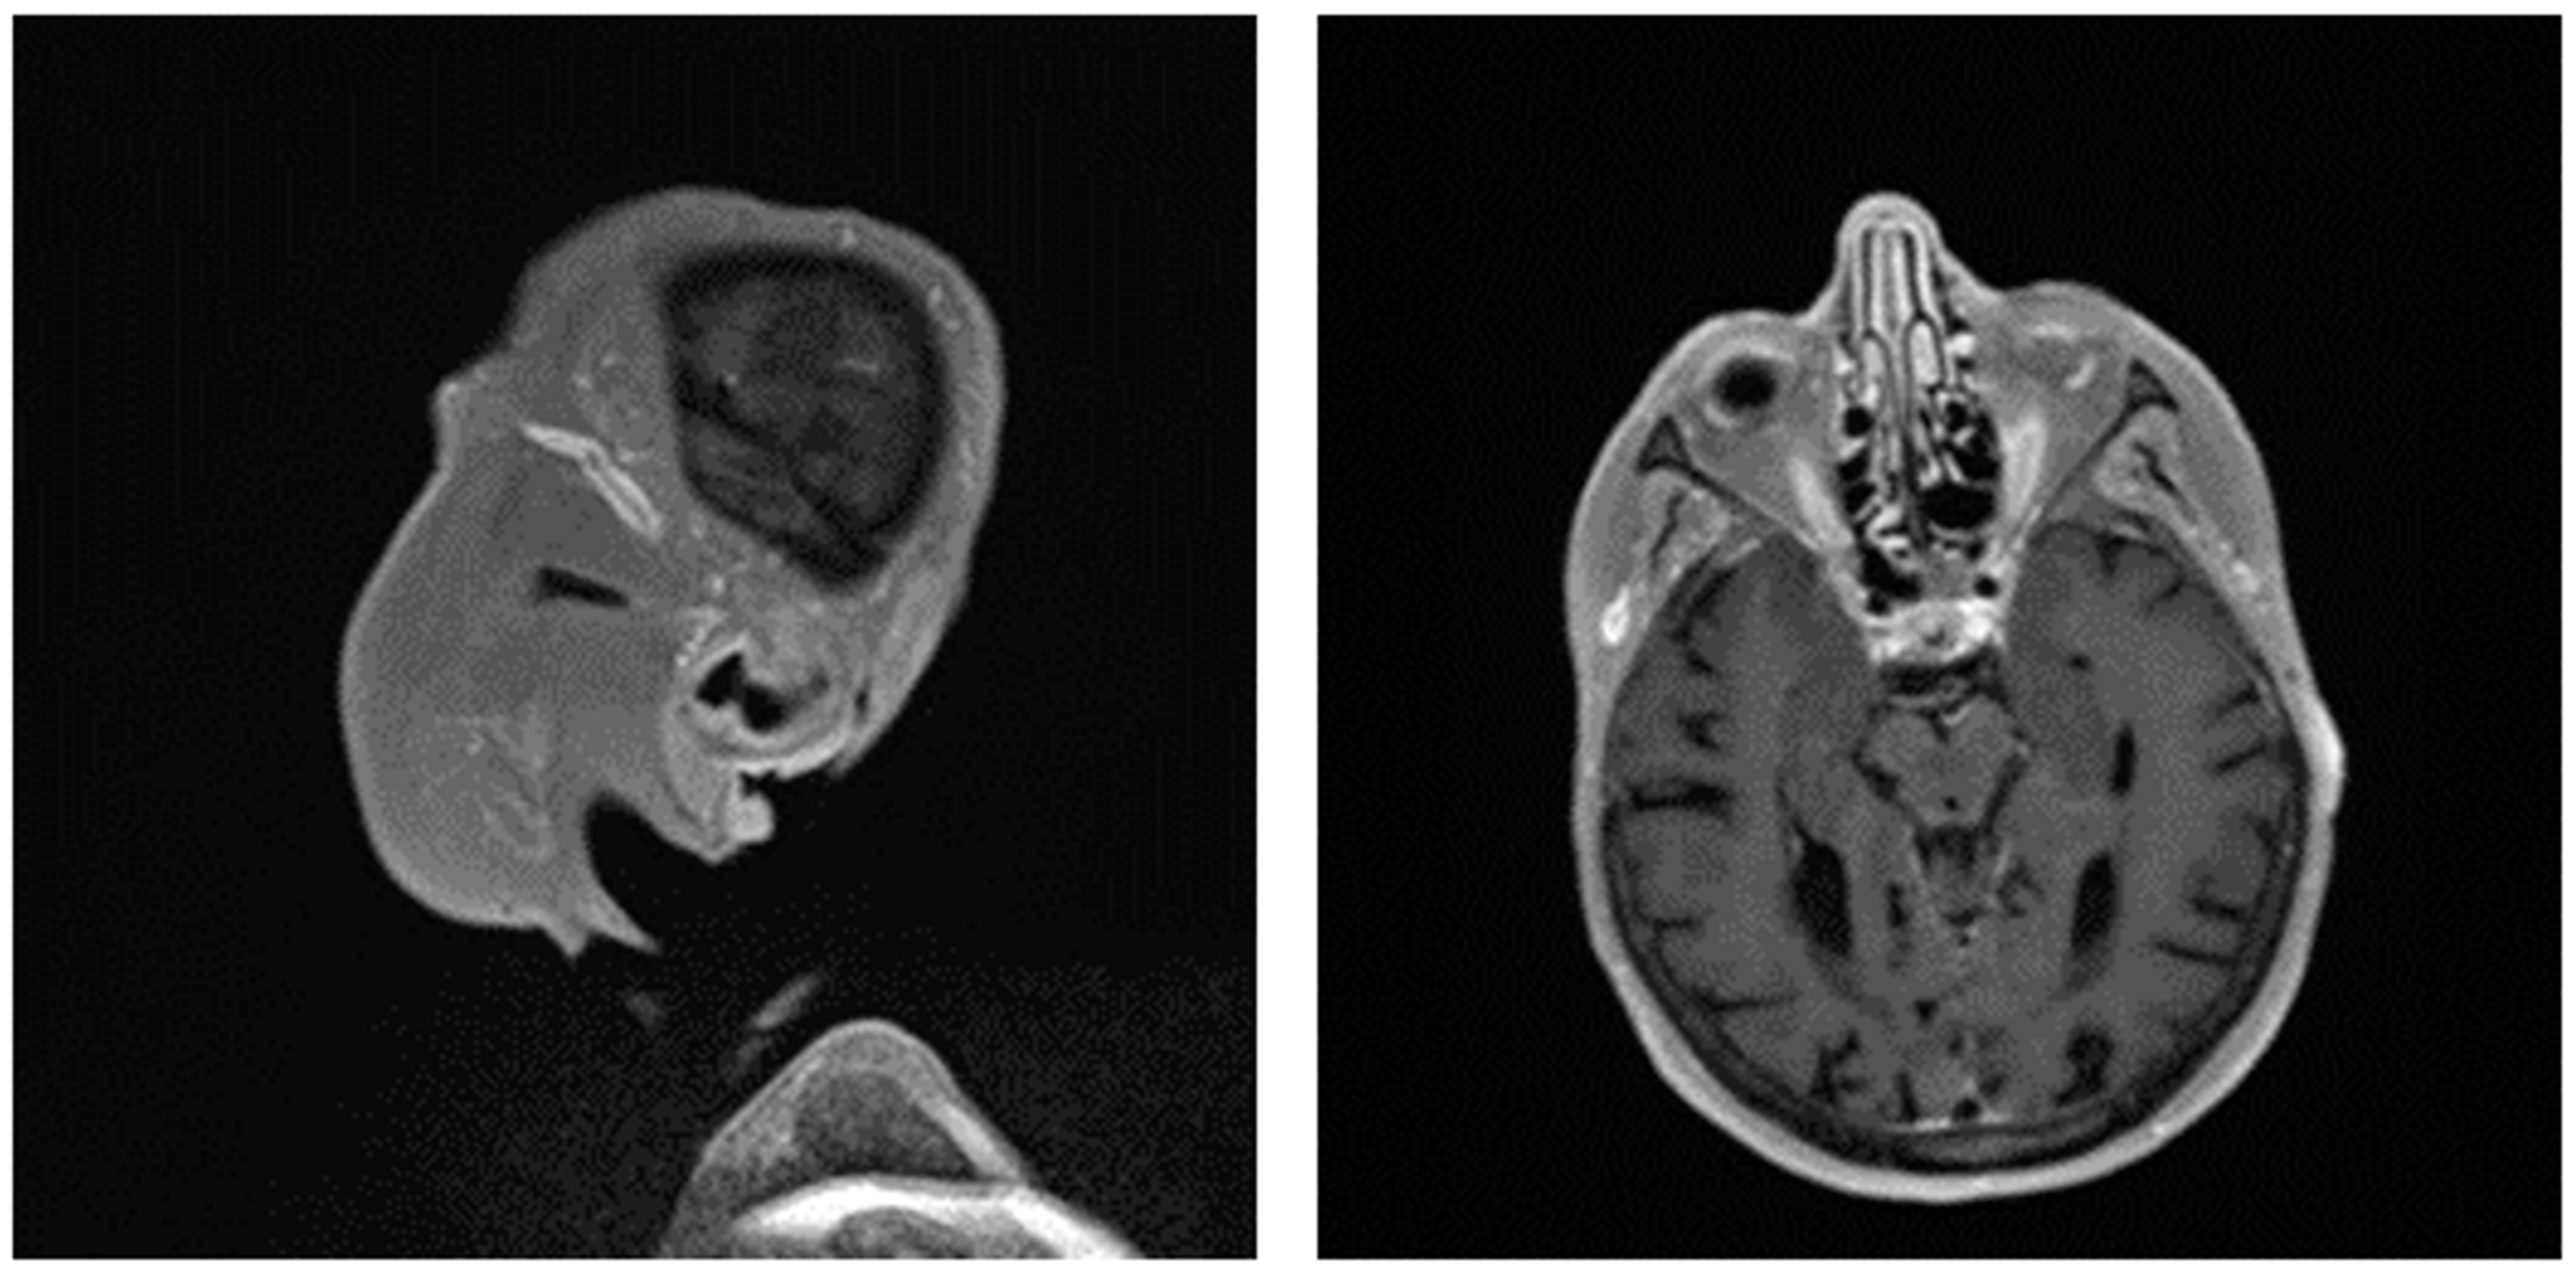

Giant cell arteritis (GCA) affects typically large- and medium-sized arteries, including the carotid arteries and their extracranial branches, as well as the aorta and its branches [48]. Symptoms of GCA include headache, jaw claudication, tenderness of the temporal artery, and low-grade fever [49]. Typical complications of GCA include acute loss of vision and aortic aneurysms, which in turn can lead to more severe complications like stroke or aortic dissection [49,50]. GCA is frequently linked with polymyalgia rheumatica (PMR), characterized by muscle pain and bilateral morning stiffness in the proximal extremities. At a microscopic level, giant cells infiltrate the vascular wall, leading to an occlusion of the affected blood vessels and thus to ischemia of the tissue to be supplied [51]. The diagnosis of PMR/GCA is usually based on clinical presentation, imaging, temporal artery biopsy (Figure 2C,D, Figure 3 and Figure 4), and the ACR/EULAR classification criteria [49,52].

Figure 4. Pronounced wall thickening of the temporal arteries, as depicted on black blood magnet resonance imaging sequences (T1 space). (Courtesy of Dr. Corinna Schorn, Rheumatology Center, Rhineland-Palatinate).